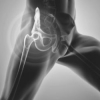

Kalça Ağrısı ve Kireçlenmesi

Kalça, bacakları üst bedene bağlayan soket eklemdir. Kalça ağrısının pek çok nedeni olabilir. Çünkü bu eklem ve kemikleri çevreleyen pek çok bağ, tendon, kas ve eklem bulunur. Bu yazımda sizlere kalça ağrısına neden olan durumlardan ve kalça ağrısının nasıl tedavi edileceğinden genel hatları ile bahsetmek istiyorum.